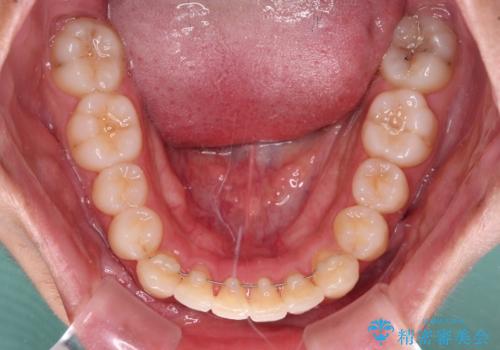

矯正治療後は、再度後戻りすることを極力回避するために、下顎前歯の舌側を細いワイヤーを用いて保定することとしました。